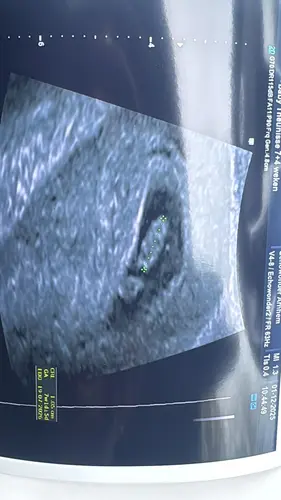

Als je vorige week maandag uitkwam op 6.3 en nu op 7.1 is dat prima. De eerste weken kan elke millimeter al een verschil van een paar dagen aangeven. Het is nog zó klein dat er met 3x meten door dezelfde persoon op hetzelfde moment zelfs 3 verschillende termijnen op het scherm kunnen komen te staan. De zwangerschapsduur wordt niet voor niks pas definitief bepaald bij de termijnecho (tussen de 10-12 weken).